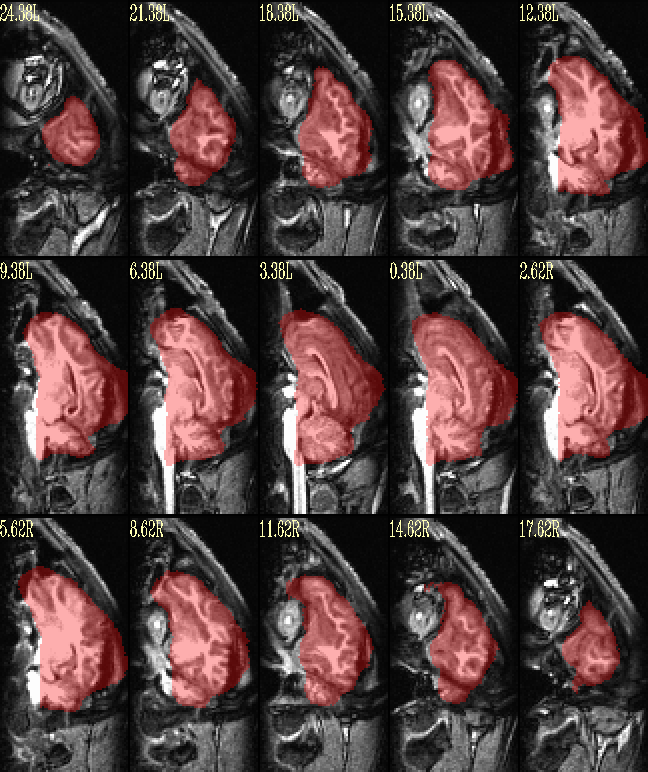

I am currently trying to use @animal_warper to align a dataset to a template, save the warp and inverse warp, apply those transforms to follower datasets like atlases, segmentations, and masks, and do skull stripping by warping a template brain mask back to native space. I looked at both the datasets in ITK snap and both the native and template centers are way apart. So I used itksnap to clisely register them to have the same center as the template space and use animal warper. But everytime i run following code, I get the following error. Could some please shine light on why this is happening. I perfromed this before brining the centers of both the datasets close and wide apart.